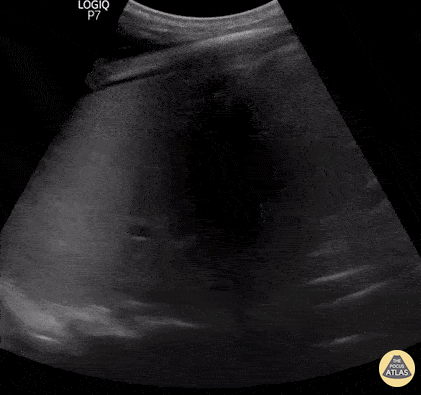

Pulmonary - PLAPS consolidation

23 yo male, comes to Emergency Department with cough, fever and dyspnea. Lung Ultrasound in the right PLAPS point show this beautiful image: a large consolided lung with dynamic air bronchograms - numerous tortuous hyperechoic opacities that move with the respiratory cycle. This finding has a specificity of 94% and a positive predictive value of 97% for pneumonia as the cause of the consolidation. Renato Tambelli @JediPocus @R_Tambelli